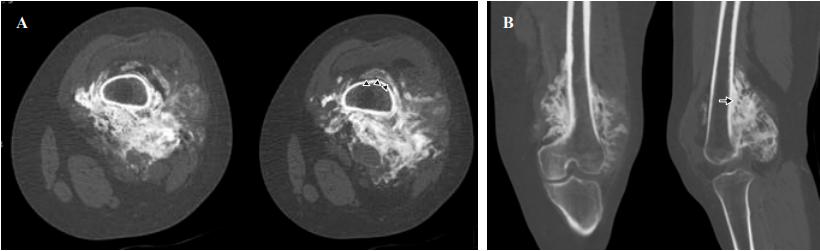

计算机断层扫描显示股骨后表面有一个皮质旁的非均匀肿瘤。存在有低密度区和高密度区。骨髓不受影响(图2)。

图2、计算机断层扫描。轴向切面(A),多平面重建(B)。在干骺端后表面和股骨干远端三分之一处存在皮质旁肿瘤,显示大量骨化,几乎包围了整个股骨周长,识别出绳状(箭头)和皮质增厚的迹象(箭头)。骨髓未受到影响